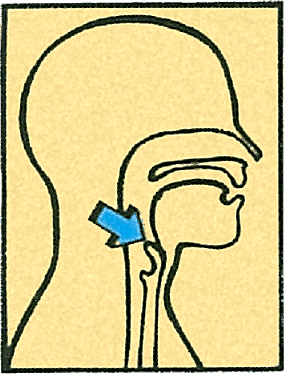

– Молли, смотри! – внезапно воскликнул Макс, и Бакстер повернулся к нему с воскресшей надеждой. – Помнишь, у нас было воспаление миндалин? Вот они – миндалины!

Его палец упирался в изображение головы с широко разинутым ртом.

В глубине рта за коренными зубами с обеих сторон виднелись два бугорка с надписью «Миндалины».

Молли наклонилась, чтобы поглядеть на них в лупу. Внезапно их всех троих озарила нестерпимо яркая вспышка. Они услышали удар грома, и вокруг сомкнулся непроницаемый мрак. Они проваливались в безмолвную бездну, кувыркались и громко кричали.

– Тогда это надгортанник, – сообщил Макс. – Я видел его в книге. Он предохраняет дыхательное горло, то есть трахею, когда мы глотаем, – чтобы пища не попала в легкие и мы не подавились.

– Туда Бакстер и провалился, – сказала Молли. – На вдохе. Значит, второй туннель для пищи. – Она указала на пропасть, в которую обрушился водопад.